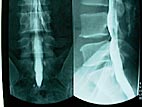

造影剤を入れている時撮ったレントゲン。よくわかるでしょ。